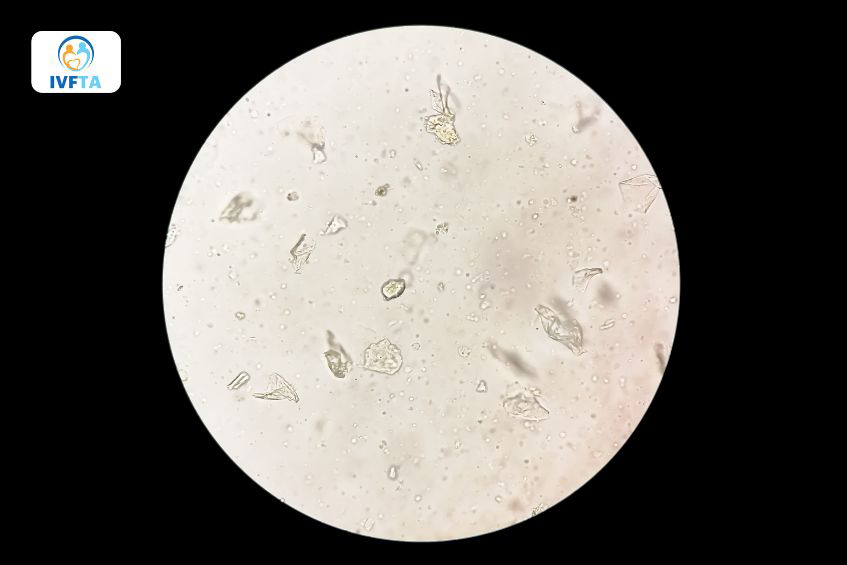

Qua kết quả tinh dịch đồ cho thấy phần lớn tinh trùng của người nam đều có hình dạng bất thường sẽ kết luận là quái tinh hay tinh trùng dị dạng. Tinh trùng của nam giới khỏe mạnh bình thường sẽ có đầu hình bầu dục, đuôi dài. Tinh trùng bất thường có thể có hình dạng đầu kỳ lạ, có thêm đầu hoặc thêm đuôi.

Những tinh trùng có hình dạng bất thường sẽ bị suy giảm khả năng di chuyển, từ đó ảnh hưởng đến khả năng thụ thai. Nguyên nhân dẫn đến quái tinh phần lớn đến từ yếu tố di truyền.